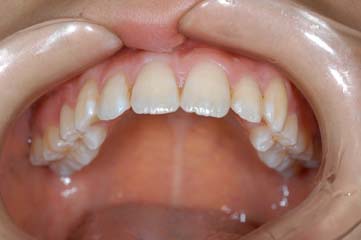

治療後

上下顎の前突感改善のため第一小臼歯の抜歯を行い最終排列を行いました。